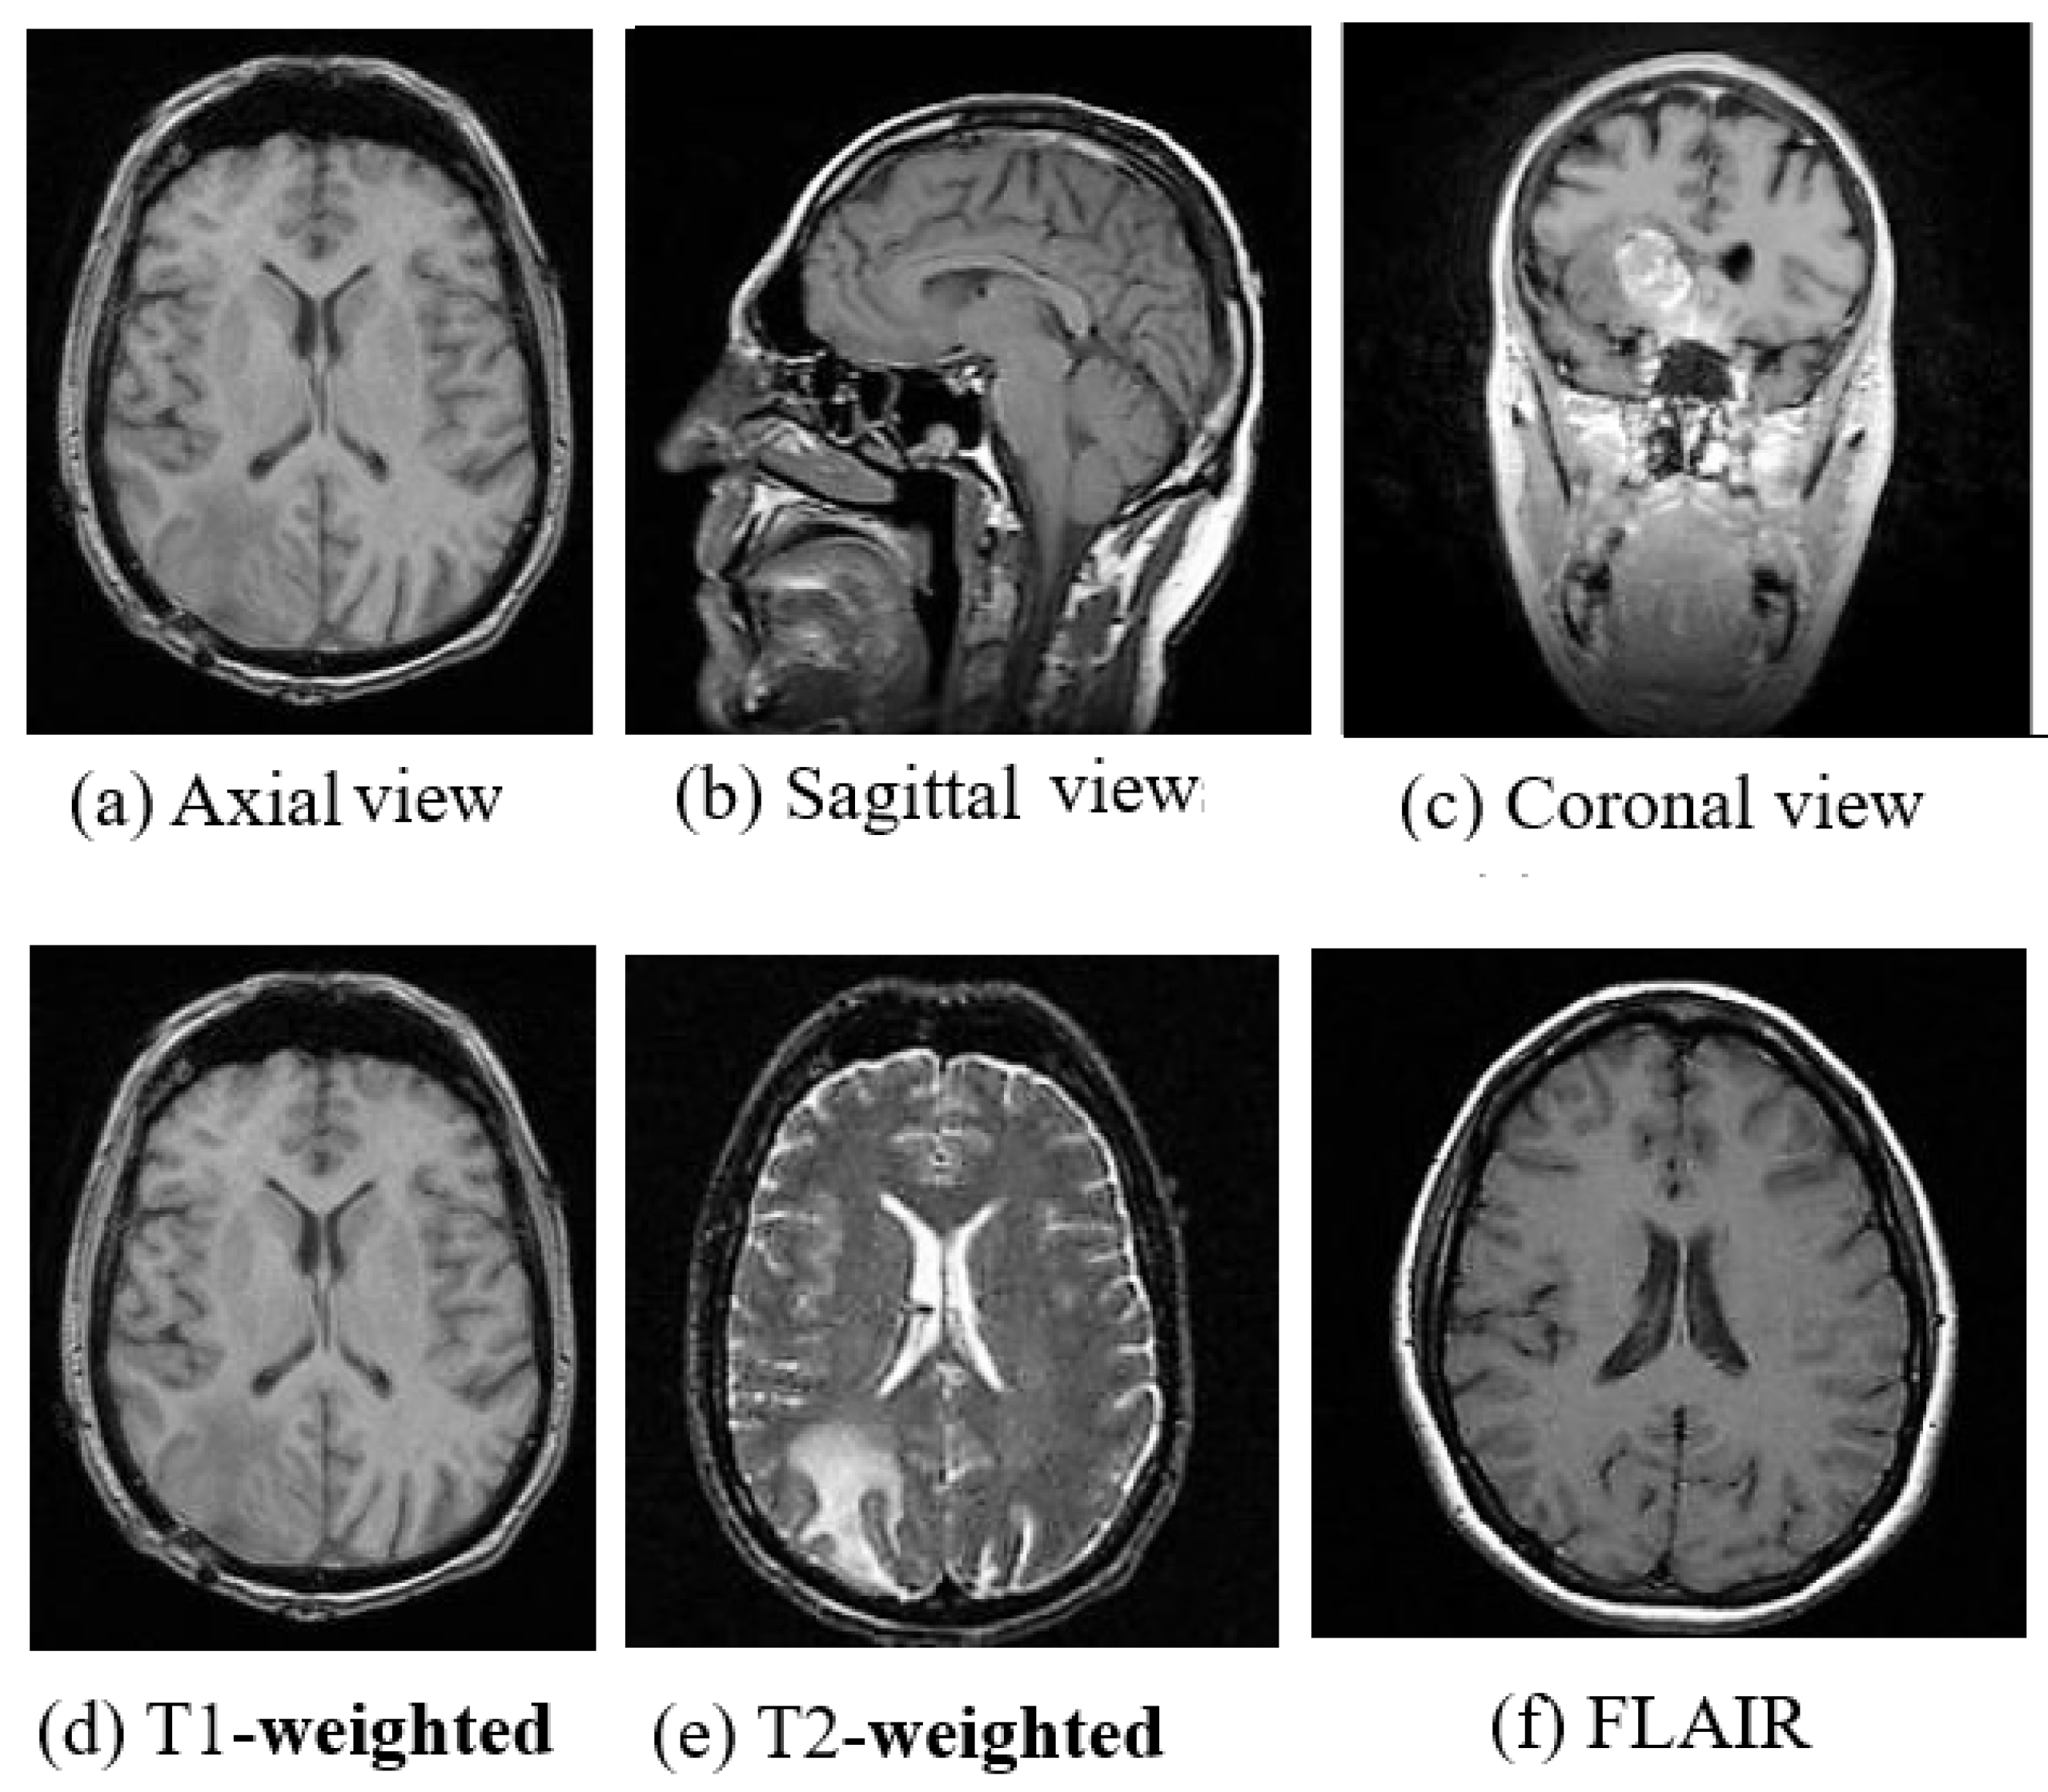

3.2. Magnetic Resonance Imaging

5.3. Imaging Test

7. Brain Cancer and Other Brain Disorders

7.1. Stroke

7.2. Alzheimer’s Disease

7.3. Parkinson’s Disease

7.4. Leukoaraiosis

7.5. Multiple Sclerosis

7.6. Wilson’s Disease